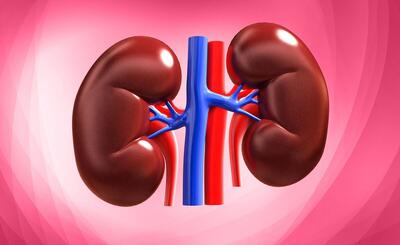

رابطه مصرف مسکن در بیماران میگرنی و آسیب به کلیه

یک جراح کلیه و پروستات با اشاره به پیشگیری و درمان بیماریهای کلیوی توضیحاتی ارائه کرد.

راه های محافظت از سلامت کلیه ها

رکنا: سلامت کلیه ها بسیار مهم است.

اهمیت تستهای سالانه عملکرد کلیوی از ۴۰ سالگی به بعد

نارسایی مزمن کلیه یک بیماری خاموش است که فرد مبتلا ممکن است سالها از آن بیاطلاع باشد؛ علل ایجاد کننده این بیماری، اغلب به بیماریهای دیابت و فشار خون بالا بازمیگردد.